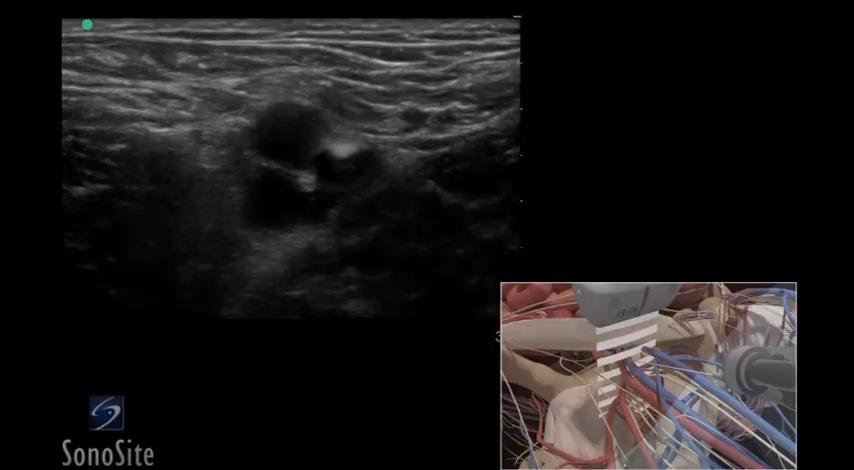

超声引导平面内锁骨下静脉穿刺置管

331 #锁骨下静脉穿刺